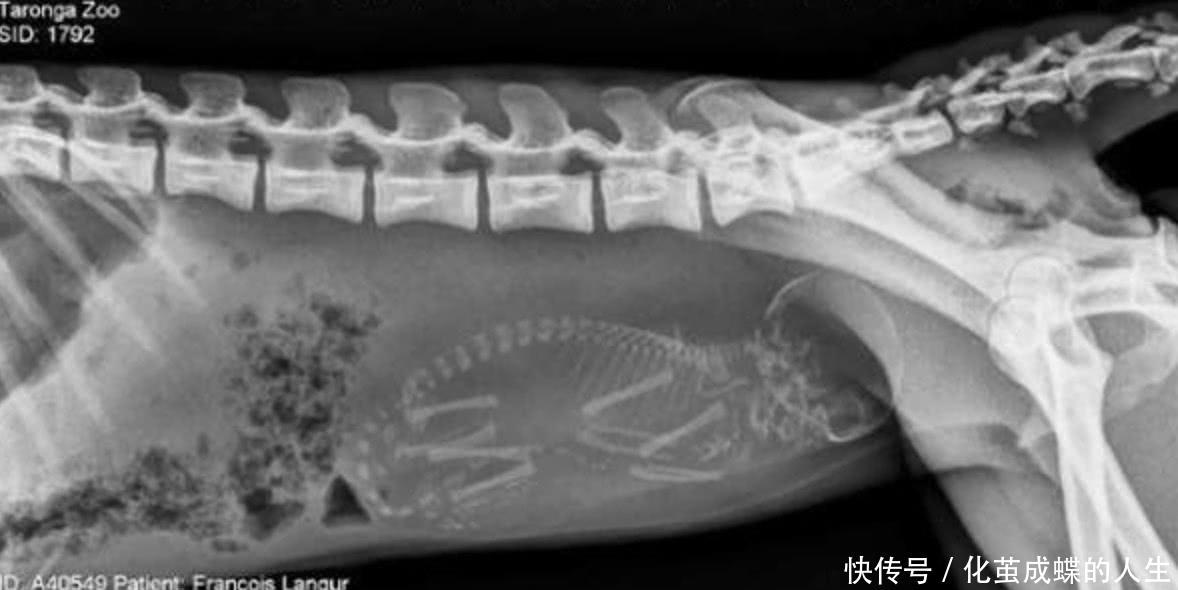

当动物怀孕时,胎儿的形状是什么?通过这些x光可以清楚地观察到动物怀孕的数量和形状。这只乌龟的x光片可以清楚地看到乌龟体内的蛋~ < p >

这是一只怀孕的几维鸟,它是新西兰的国鸟虽然它的名字里有“鸟”这个词,但是它的翅膀已经完全退化了,它通常在一两年内一次产一个或两个蛋。尽管它的大小与普通母鸡相似,但它的蛋比鸡蛋大五倍,相当于它重量的三分之一。根据比例,它可以说是非常大的鸡蛋!< p>

鬃毛狮蜥,主要栖息于沙漠环境,半树栖昼间它能为每个胎儿产生大约11-26个卵子。从照片中,我们可以清楚地看到鬃毛狮蜥中有许多卵。< p>

幼鲨已经开始在母亲的肚子里激烈竞争。他们互相残杀。鲨鱼的子宫里一次大约有20个胚胎。幼鲨会吃掉十几个兄弟姐妹和17000多个蛋。自幼鲨出生以来,它们就有丰富的狩猎经验。